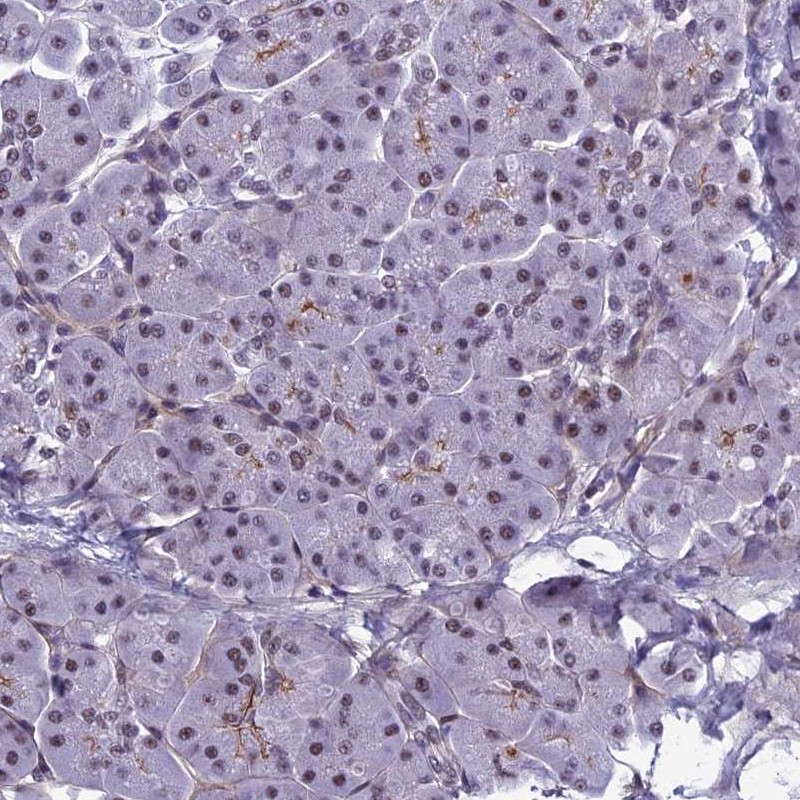

Immunohistochemistry analysis in human cerebral cortex and pancreas tissues using Anti-RSRC1 antibody. Corresponding RSRC1 RNA-seq data are presented for the same tissues.